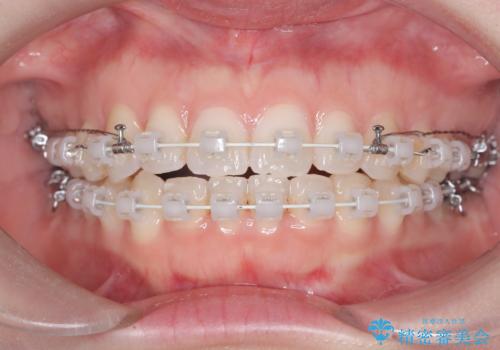

審美ワイヤー矯正とTAD併用による犬歯の遠心移動

- 歯並びの乱れを改善したいと来院されました。精密検査の結果、犬歯を奥へ動かすことで、より美しい口元と安定した咬み合わせが得られると診断。患者様のご希望から、目立ちにくい審美ワイヤー矯正を採用し、効率的な歯の移動のために**リンガルアーチとTAD(矯正用アンカースクリュー)**を併用する計画を立てました。これにより、抜歯せずにスペースを確保し、犬歯をスムーズに遠心へ移動させます。

今回の矯正では、装置が目立たないよう透明なブラケットと白いワイヤーを使用。さらに、効率的な歯の移動のために、歯の裏側にリンガルアーチを設置しました。また、確実な奥歯の移動のために**TAD(矯正用アンカースクリュー)**を一時的に使用。これにより、犬歯を狙った位置へ正確に動かすことが可能に。目立ちにくい装置で快適に過ごしながら、理想的な歯並びと咬み合わせを獲得していただけました。